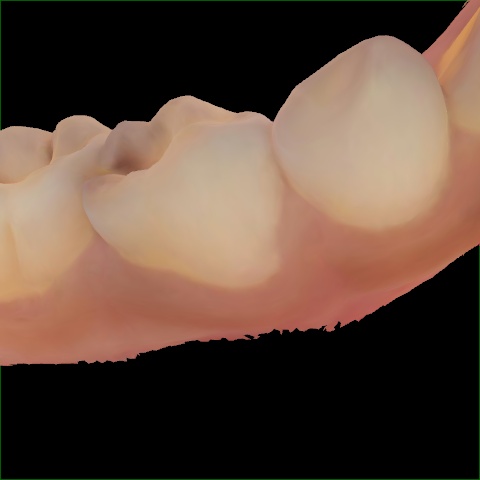

Annotated as "Good"